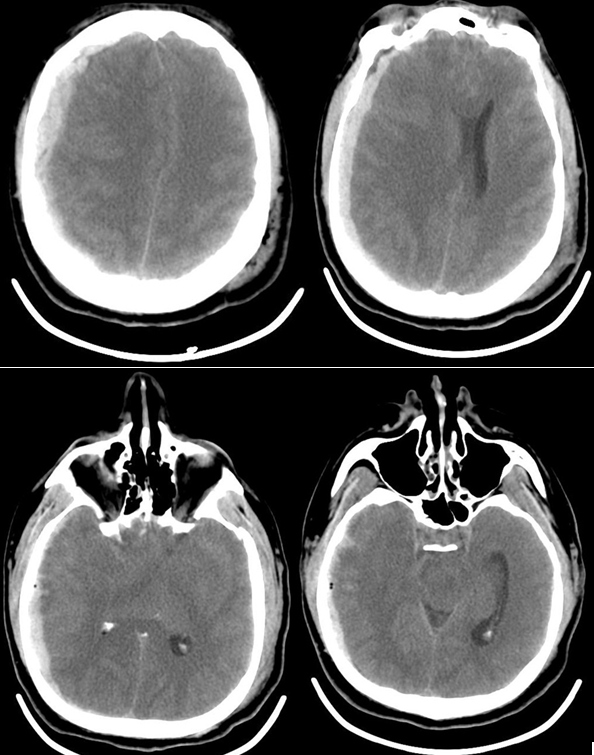

Пациент К., 42 года поступил в отделение реанимации Института нейрохирургии с диагнозом: «Острая тяжелая закрытая сочетанная черепно-мозговая травма, острая субдуральная гематома в правой лобно-теменно-височной области, ушиб головного мозга средней степени, травматическое субарахноидальное кровоизлияние, перелом чешуи височной кости слева; перелом левой ключицы». При поступлении уровень сознания оценивался по ШКГ 5 баллов. В ответ на болевой стимул отмечалось приведение в руках, разгибание в ногах, анизокория D>S, фотореакция вялая, кашлевой рефлекс угнетен. По данным компьютерной томографии головного мозга: справа в лобно-височно-теменной области определялась субдуральная гематома, срединные структуры смещены влево, желудочковая система и охватывающая цистерна компримированы. Также выявлялись признаки САК и перелом чешуи височной кости слева (рис.1).

Рис. 1 КТ головного мозга пациента К., 42 года